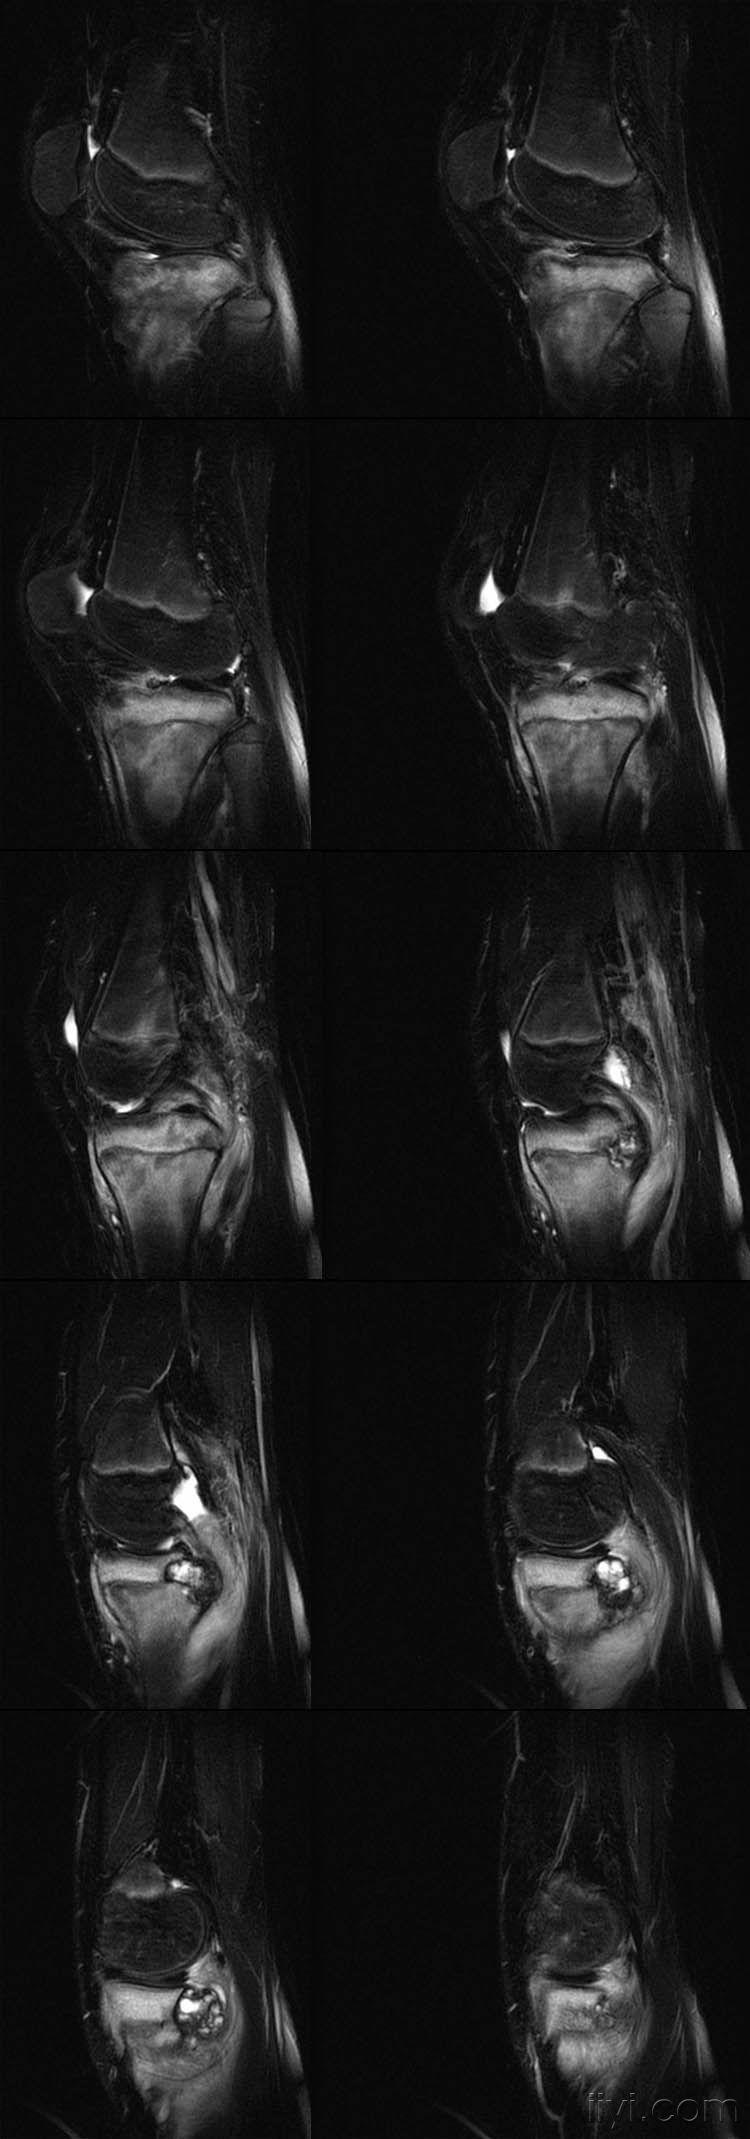

女,14岁,膝关节外伤后疼痛4月余。

向老师学习,恶性肿瘤可能,骨肉瘤?